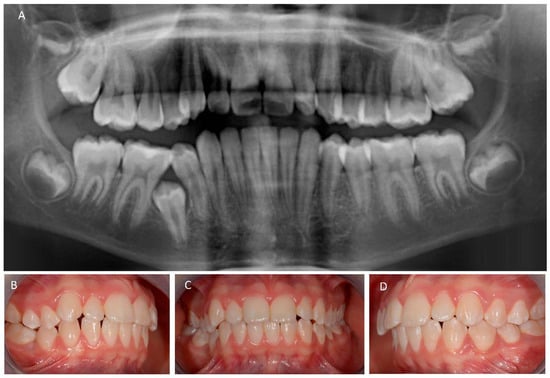

2. Case Presentation